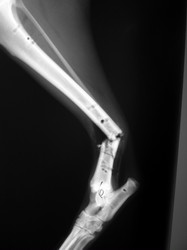

Fijación Externa

PRÁCTICAS CURSO DE FIJACIÓN EXTERNA PERFECCIONAMIENTO.

Híbrido.